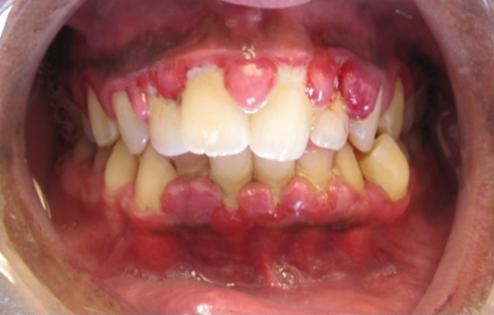

Gingivitis is a common and mild form of gum disease (periodontal disease) that causes irritation, redness and swelling (inflammation) of your gums. It can lead to much more serious gum disease (periodontitis) and eventual tooth loss. The most common cause of gingivitis is poor oral hygiene.

La gingivitis es una enfermedad reversible que afecta a las encías, que como consecuencia de un proceso de inflamación, sangran, cambian de color (encías rojas) y se vuelven más grandes. Está causada por una infección que crean las bacterias. Es una enfermedad inflamatoria periodontal reversible porque no llega a afectar el hueso que rodea el diente.